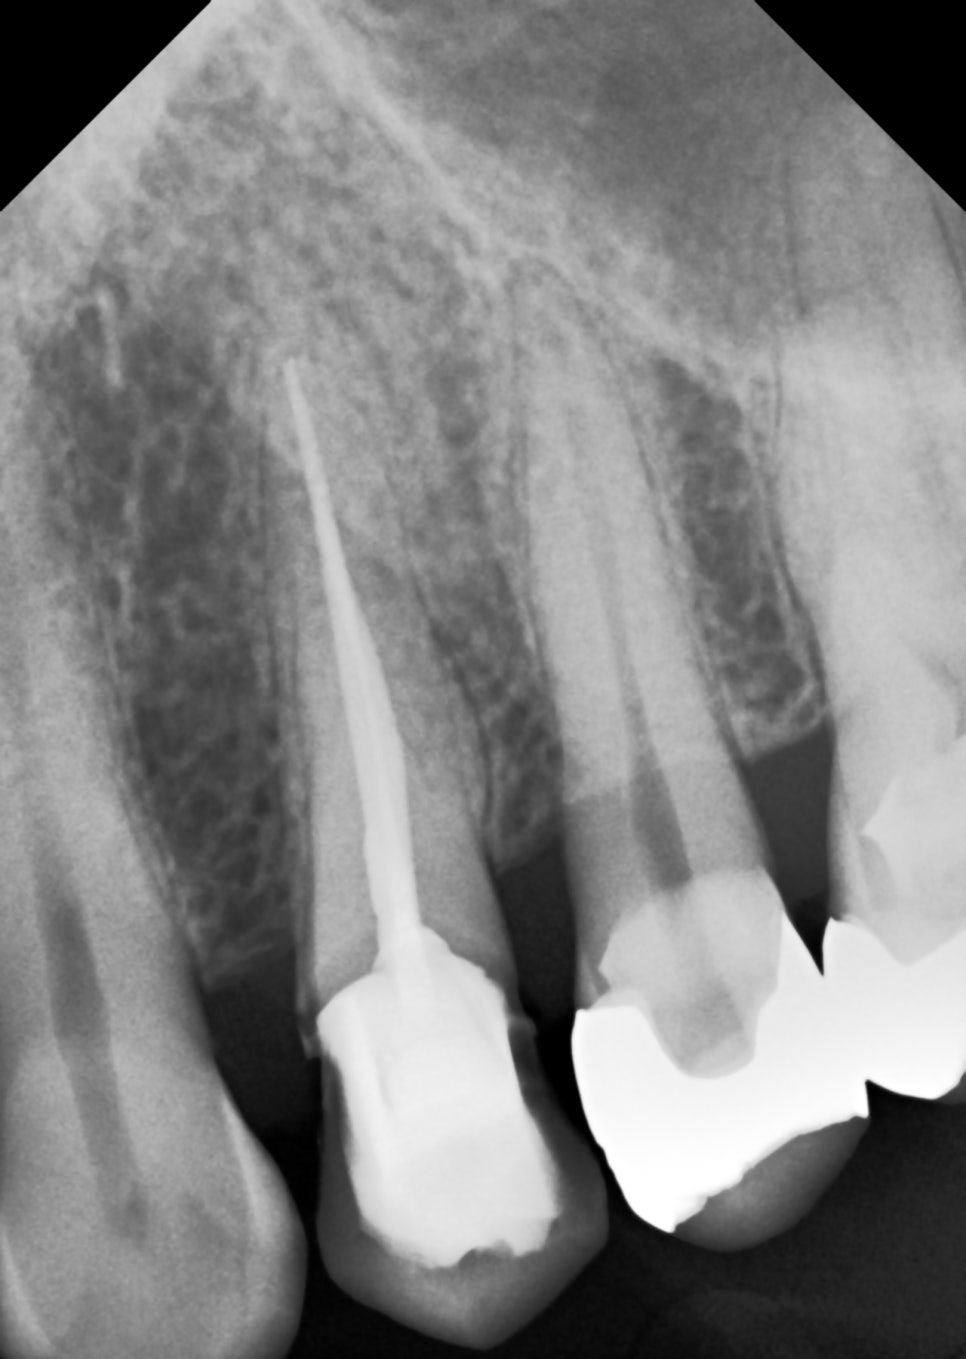

촬영 : 240708

위 사진처럼 충치가 진행되고 있었고,

치료를 권해드렸으나

6개월 뒤에 하시겠다며 귀가하셨어요.

촬영일 : 250901

파노라마와 구내 사진, 탐침 검사로 확인하니

손상이 생각보다 컸고

충치가 깊이 진행되었어요.

내용물을 정리해 보니 신경(치수)이

이미 오염되어 있었어요.

신경치료(근관치료)가 먼저였죠..

근관치료부터 시작했어요.

러버댐으로 침과 피를 철저히 차단하고

감염된 치수 조직을 제거한 뒤

근관을 확대·성형해 세척과 충전을 준비했어요.

길이 측정을 반복하고 밀폐를 진행했죠^^

약해진 몸통(코어)을 다시 세워야 오래 가요.

그래서 UHMWPE 섬유 포스트로 기초를 다지고

내부는 everX(FRC 보강 레진)로 채워

균열 전파를 억제했어요.

촬영일 : 250901 / 250915